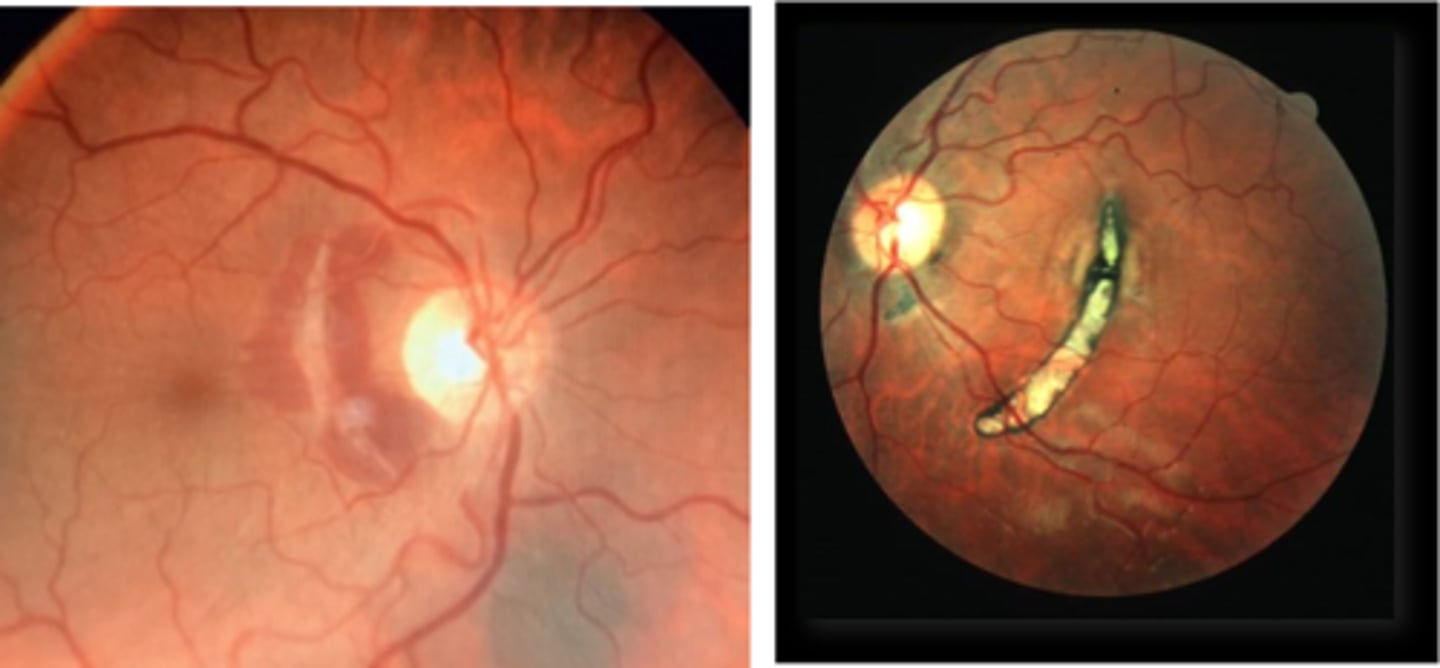

What findings of toxoplasmosis are seen here?

retinal vasculitis

exudative scar

focal, hazy vitritis and retinitis

What findings of toxoplasmosis are seen here?

latent scars